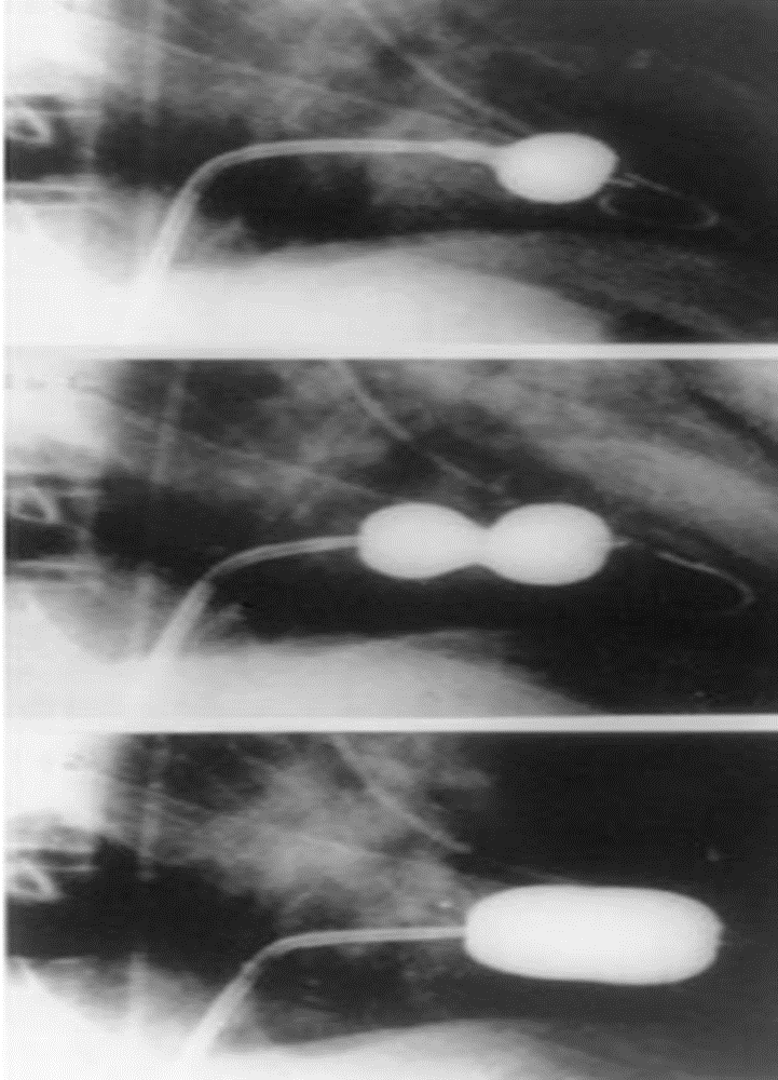

Percutaneous mitral valve balloon commissurotomy (PMBC)

Percutaneous mitral valve balloon commissurotomy (PMBC) [15]

- PMBC is the preferred intervention in most patients with severe MS.

- A balloon catheter is advanced percutaneously through the mitral valve and inflated to break open commissural stenosis and increase the mitral valve area. The Wilkins score is used to determine eligibility.

Surgery

- Surgical interventions include open commissurotomy and mitral valve (mechanical or bioprosthetic) replacement.

Indications- Unfavorable anatomy for PMBC

- Presence of thrombus in the left atrium

- Mixed valvular disease (e.g., severe MR, tricuspid disease)

- Contraindicated if there is a prohibitively high surgical risk